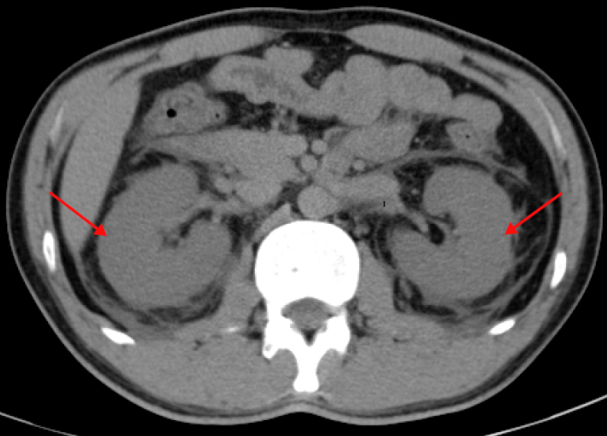

辅助检查显示:白细胞计数升高[22.6×109/L,N:(3.5~9.5)×109/L],血细胞比容降低(36.00%,N:40.00%~50.00%),血小板减少[48.0×109/L,N:(100.0~300.0)×109/L],异性淋巴细胞10%,降钙素原(prcalcition, PCT)升高(9.23 ng/mL,N:0.00~0.065 ng/mL)和C反应蛋白升高(60.4 mg/L,N:<10.0 mg/L)。血清白蛋白降低(28.4 g/L,N:40.0~55.0 g/L),血清肌酐升高(387 μmol/L,N:64~104 μmol/L),低钠血症(128.9 mmol/L,N:137.0~147.0 mmol/L)和低氯血症(92 mmol/L,N:99~110 mmol/L)。天门冬氨酸氨基转移酶(AST,26 U/L,N:5~40 U/L)和丙氨酸氨基转移酶(ALT,35 U/L,N:5~50 U/L)未升高。心肌酶谱示:肌酸激酶同工酶升高(26 U/L,N:0~24 U/L)、乳酸脱氢酶升高(522.1 U/L,N:120.0~250.0 U/L),肌酸激酶未升高。全腹部CT平扫示:双肾肾周筋膜增厚渗出明显,提示炎症考虑(图 1)。

| 图 1 入院时腹部CT提示双肾肾周筋膜增厚渗出明显(红色箭头) |